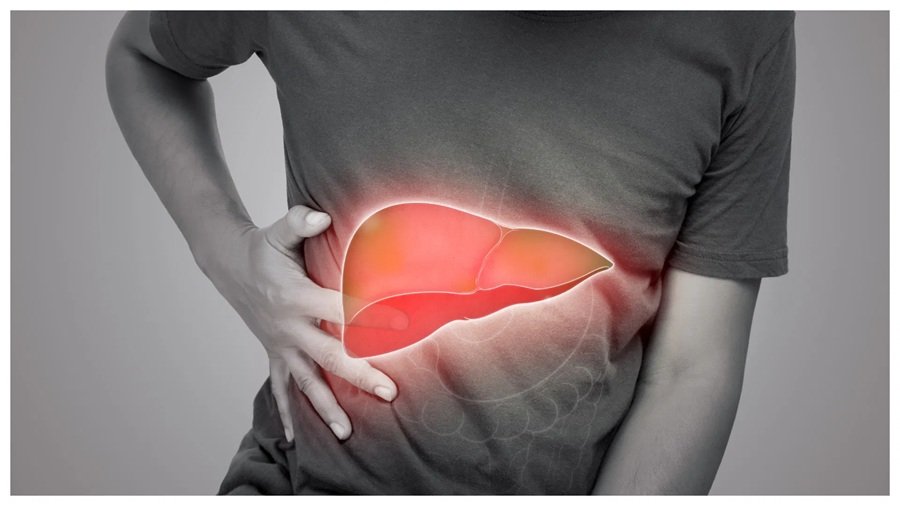

दोस्तो आज हम सब अपने कामकाज और जीवन की भागदौड़ में इतने व्यस्त हो गए हैं कि अपने खान पान और जीवनशैली पर ध्यान नहीं दे पाते हैं, जिसकी वजह से कई प्रकार की स्वास्थ्य परेशानियां उत्पन्न होती हैं, फैटी लिवर एक आम समस्या हैं, यह कंडीशन अक्सर बिना किसी खास लक्षण के चुपचाप बढ़ जाती है। अगर इसे लंबे समय तक नज़रअंदाज़ किया जाए, तो इससे लिवर फाइब्रोसिस, सिरोसिस या लिवर कैंसर जैसी गंभीर दिक्कतें हो सकती हैं। लेकिन एक अच्छी डाइट आपके फैटी लीवर की परेशानियां दूर कर सकते हैं, आइए जानते हैं किन चीजों का सेवन करें